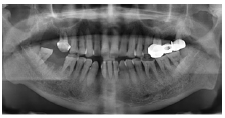

X线显示:全口牙槽骨广泛性混合吸收至根长的1/3~2/3(图4)。

图4  病例2患者曲面断层片